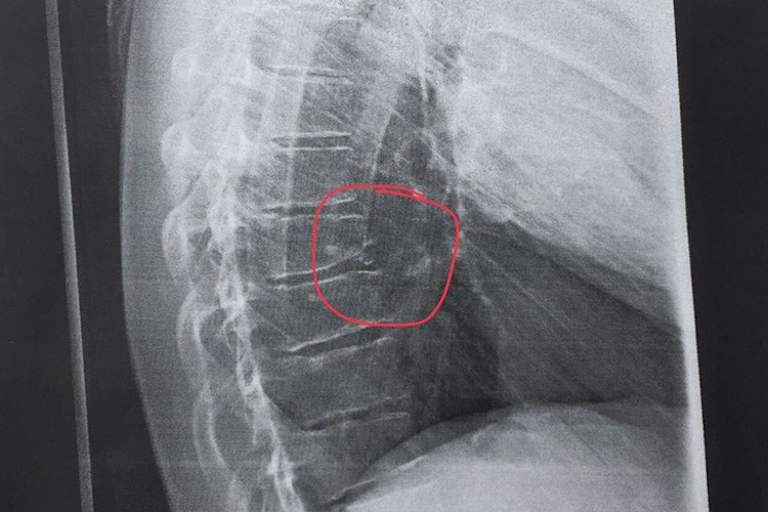

Schmerzgeplagt begab sich Smolinski anschließend in ärztliche Behandlung. Da Martins Orthopäde anhand von Röntgenaufnahmen keine Entwarnung geben konnte, musste ein MRT weitere Aufschlüsse bringen. Das Resultat der Untersuchungen ergab, dass sich der Olchinger neben einer starken Rippenprellung auch eine Knochenabsplitterung an der Brustwirbelsäule zugezogen hat, die zu einer Schwellung im Bereich der Wirbelsäule führte. Die Ärzte verordneten Smoli nun einige Tage Ruhe, damit die Schwellung zurückgehen kann und die Prellungen nachlassen. Anschließend bekommt er gezielte Physiotherapie und Rückentraining, um schnellst möglichst wieder schmerzfrei Motorrad fahren zu können. Den geplanten Start bei der Paar-Europameisterschaft in Ungarn am morgigen Samstag musste Smolinski auf Anraten der Ärzte absagen. Er wird von Ronny Weiß ersetzt, der das Rennen gemeinsam mit Valentin Grobauer bestreitet.